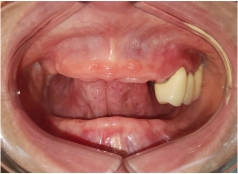

• Tình trạng răng trước đây:Mất hết răng 2 hàm, sử dụng hàm tháo lắp lâu năm bị tiêu xương

Là người có cơ địa nhạy cảm và tâm lý luôn sợ đau, vì vậy cô Thanh Hương đã lựa chọn làm hàm tháo lắp khi bị mất răng thay vì cấy ghép Implant. Tuy nhiên, những biến chứng sau đó lại khiến cô hối hận vì quyết định của mình.

Trước đây vì chủ quan trong việc ăn uống và chăm sóc răng miệng không kỹ lưỡng, dẫn tới nhiều răng của cô Hương bị sâu nặng, vỡ mẻ gần hết, bác sĩ chỉ có thể nhổ bỏ để ngăn chặn viêm tủy.

Nghĩ rằng hàm tháo lắp có thể khôi phục được phần nào khả năng ăn nhai và thẩm mỹ, nên cô chọn thực hiện. Thế nhưng, chỉ sau một thời gian sử dụng, cô mới nhận ra có quá nhiều nỗi bất tiện.

Đầu tiên, sức nhai của Hương bị giảm đi nhiều. Do răng tháo lắp không cố định, lỏng lẻo, hầu như không thể ăn được các đồ cứng, dai, càng cố nhai thì càng gây đau nhức. Vì vậy, cô phải dần từ bỏ nhiều món ăn yêu thích.